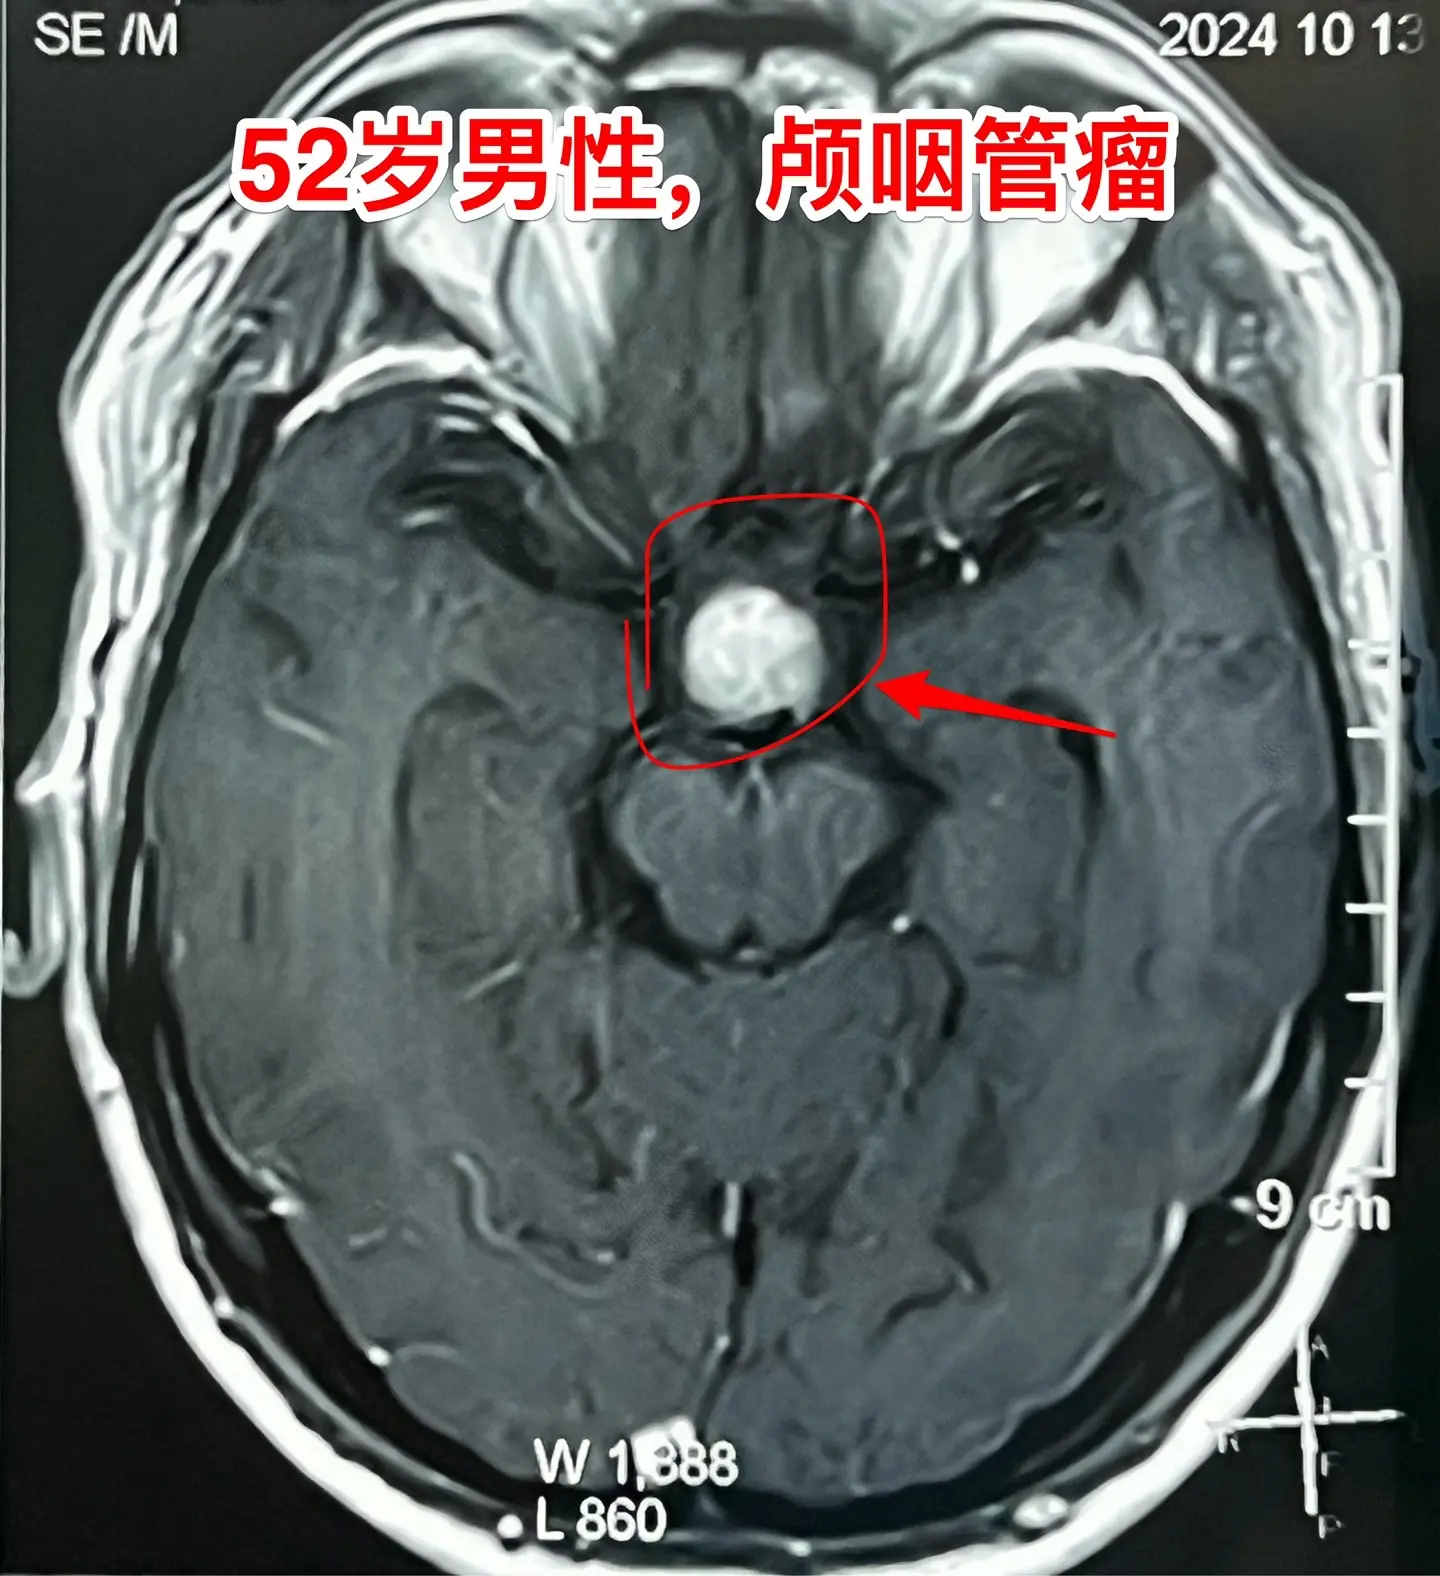

乳头型颅咽管瘤。52岁的重庆市男性,因为头痛到医院检查磁共振,居然发现...